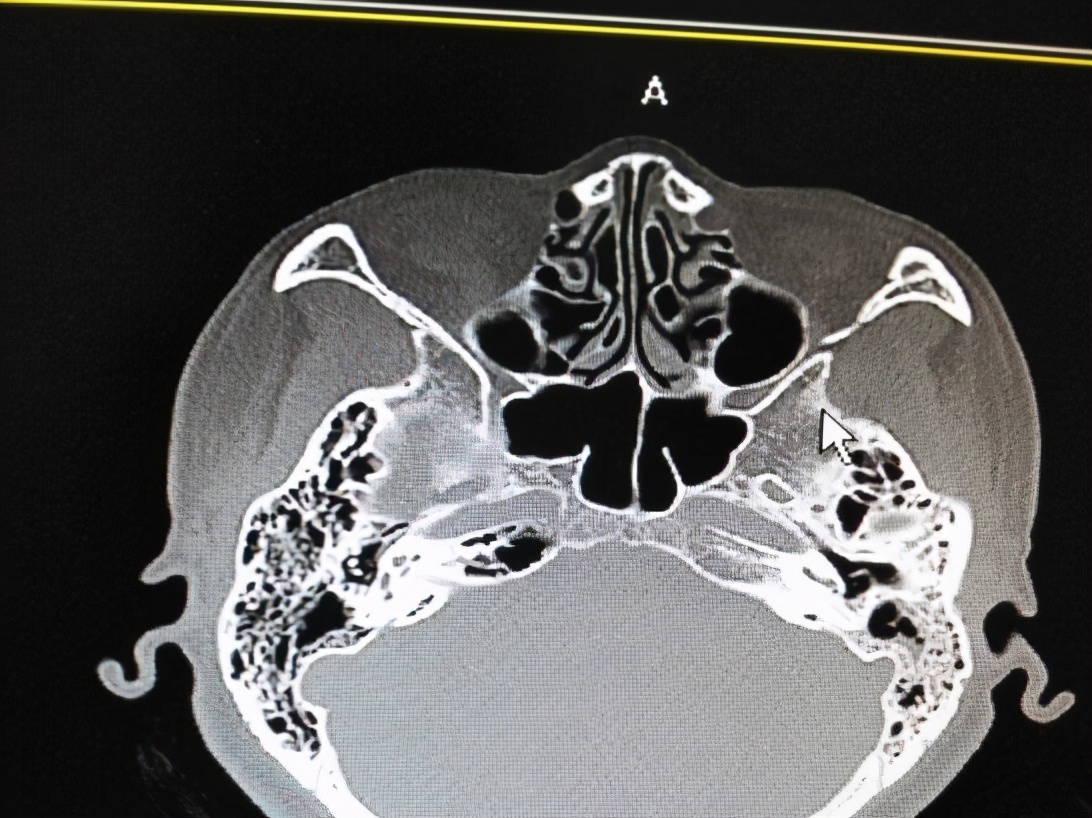

4、必要时做颞骨CT检查,可以看见是否有骨质破坏。